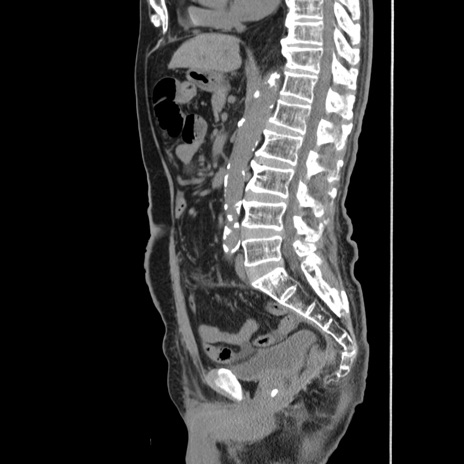

症例24(矢状断像)

【症例】80歳代男性

【主訴】左側腹部痛、嘔吐

【現病歴】本日早朝より左腹部に痛みあり。昼頃嘔吐認めたため、救急要請。

【既往歴】直腸癌(Mile手術)、胆摘

【身体所見】意識清明、BT 35.9℃、BP 221/93mmHg、SpO2 97%(RA) 、腹部:左ストーマ周囲に限局性の腹部膨隆あり。 膨隆部自発痛・圧痛あり・軟。

【データ】WBC 7700、CRP 0.09